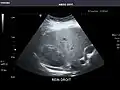

Aorta

Aorta: Visualized portions normal in caliber, 16 x 15 mm.

It can be used on the abdominal aorta to detect or exclude abdominal aortic aneurysm. For this purpose, the standard aortic measurement for abdominal aortic aneurysm is between the outer margins of the aortic wall.[4]